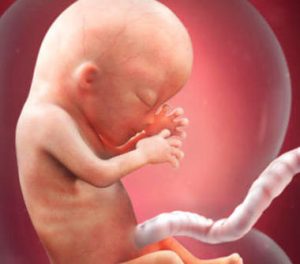

Inizia un nuovo trimestre e una nuova fase del processo di gestazione di questa piccola creatura che vive nel vostro utero. Alla tredicesima settimana di gravidanza, misura tra i 6,5 e i 10 centimetri e il suo peso oscilla dai 13 ai 20 grammi. Il suo viso inizia ad assumere i suoi particolari lineamenti e si verificano ulteriori cambiamenti che ripassiamo a seguire. È incredibilmente emozionante!

Gli occhi, prima molto separati tra loro, e le orecchie, che fino alla settimana precedente si trovavano molto più indietro, assumono la loro posizione definitiva. Oltre a ciò, vi è un dettaglio davvero affascinante: le sue impronte digitali si sono già formate.

Poiché in questo momento il cervello è una delle parti più sviluppate del feto, oltre alle strutture che sostengono e ricoprono gli organi, la testa costituisce la metà delle dimensioni totali del feto.

Dalla tredicesima settimana di gravidanza in poi, il suo corpo inizierà a crescere in modo più svelto per “raggiungere” la testa e ottenere un corpo proporzionato. Al momento della nascita, infatti, quest’ultima rappresenta solo un quarto delle dimensioni totali. In questa fase, inoltre, si verificano alcuni processi importantissimi relativi all’organismo del feto e alla sua futura nascita.